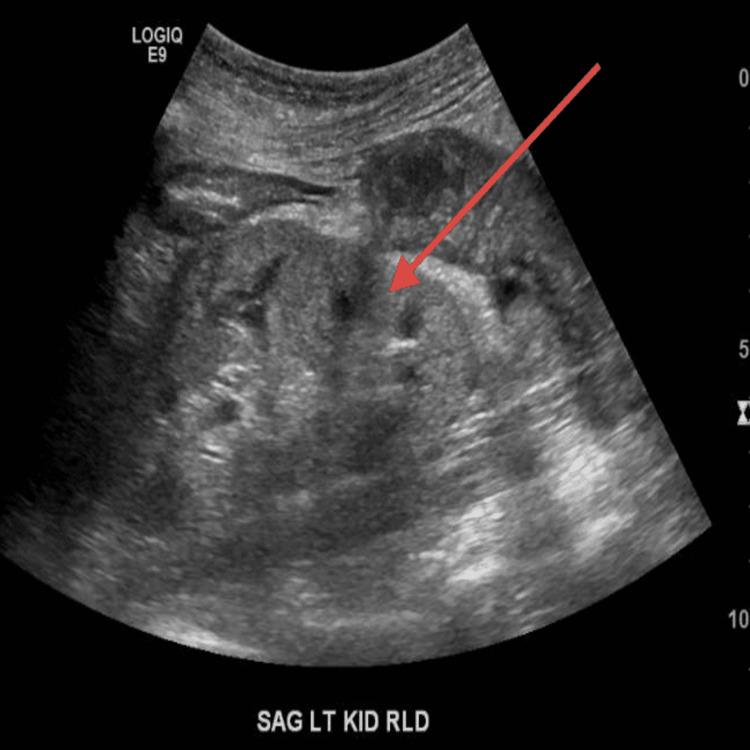

Hydralazine is a commonly prescribed medication which is used in the treatment of hypertension. While it is generally considered to be a safe and effective treatment, in rare cases it can cause a serious side effect known as hydralazine-induced vasculitis. Here we discuss this rare presentation in the form of a case report in a 67-year-old female with a past medical history of chronic obstructive pulmonary disease (COPD), congestive heart failure, hypertension, hyperlipidemia, left renal artery stenosis status post stenting who presented in the nephrology office for evaluation of recent worsening kidney function, and on further evaluation was found to have hematuria and proteinuria in the urine analysis. On further workup, she was noted to have severely elevated myeloperoxidase-antineutrophil cytoplasmic antibody (MPO-ANCA) titers with renal biopsy revealed very focal crescentic glomerulonephritis, an increased number of occlusive red blood cell cast with acute tubular necrosis. Mild interstitial fibrosis of <20% was seen and a diagnosis of drug-induced vasculitis from hydralazine was made.

肼屈嗪是一种常用药物,用于治疗高血压。虽然它通常被认为是一种安全有效的治疗方法,但在极少数情况下,它会引起一种严重的副作用,称为肼屈嗪诱发的血管炎。在此,我们以病例报告的形式讨论这一罕见病例,患者为一名67岁女性,既往有慢性阻塞性肺疾病(COPD)、充血性心力衰竭、高血压、高脂血症病史,左肾动脉狭窄支架置入术后,因近期肾功能恶化到肾病科就诊,进一步检查发现尿液分析中有血尿和蛋白尿。进一步检查发现,她的髓过氧化物酶抗中性粒细胞胞浆抗体(MPO-ANCA)滴度严重升高,肾活检显示为非常局灶性的新月体性肾小球肾炎,闭塞性红细胞管型数量增加伴急性肾小管坏死。可见轻度间质纤维化(<20%),诊断为肼屈嗪所致药物性血管炎。